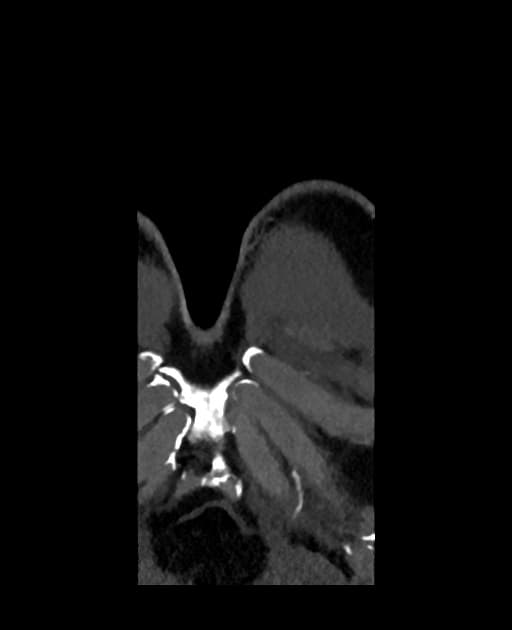

Axial C+ arterial phase

CT•Axial C+ arterial phase•1 / 229

Ca bệnhHội chứng Marfan kèm phình động mạch chủ lên và bóc tách động mạch chủ Stanford A, DeBakey I

Một trường hợp hội chứng Marfan với giãn dạng phình (aneurysmal dilation) vòng van động mạch chủ (aortic annulus) và động mạch chủ lên, kèm theo bóc tách động mạch chủ loại Stanford A, DeBakey I (Stanford A, DeBakey I aortic dissection).

Hội chứng Marfan kèm phình động mạch chủ lên và bóc tách động mạch chủ Stanford A, DeBakey I (Marfan syndrome with ascending aortic aneurysm and Stanford A, DeBakey I aortic dissection)

Hội chứng Marfan là một rối loạn trội trên nhiễm sắc thể thường liên quan đến gen fibrillin-1 (FBN1), dẫn đến suy yếu mô liên kết, đặc biệt ở hệ thống tim mạch. Bệnh nhân có nguy cơ cao bị giãn dần gốc động mạch chủ, có thể dẫn đến bóc tách động mạch chủ cấp. Trong trường hợp này, bệnh nhân biểu hiện bộ ba điển hình: dáng người cao, ngón tay dài và đau ngực cấp do bóc tách loại Stanford A, DeBakey I — nghĩa là bóc tách ở đoạn động mạch chủ lên và lan ra các đoạn xa hơn. Đây là một cấp cứu ngoại khoa. Chẩn đoán hình ảnh, thường dùng chụp cắt lớp vi tính mạch máu (CTA), giúp xác định vạt nội mạc và các lòng thật, lòng giả. Việc chẩn đoán và can thiệp sớm là rất quan trọng để ngăn ngừa vỡ mạch và tử vong.